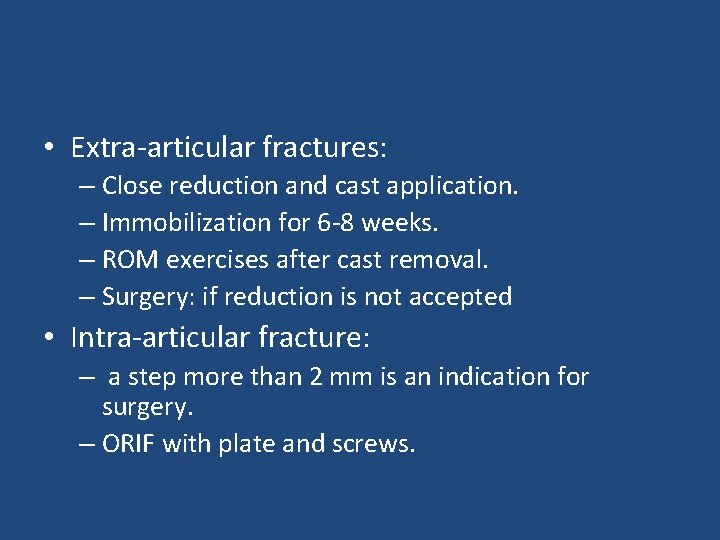

• Extra-articular fractures: – Close reduction and cast application. – Immobilization for 6 -8 weeks. – ROM exercises after cast removal. – Surgery: if reduction is not accepted • Intra-articular fracture: – a step more than 2 mm is an indication for surgery. – ORIF with plate and screws.